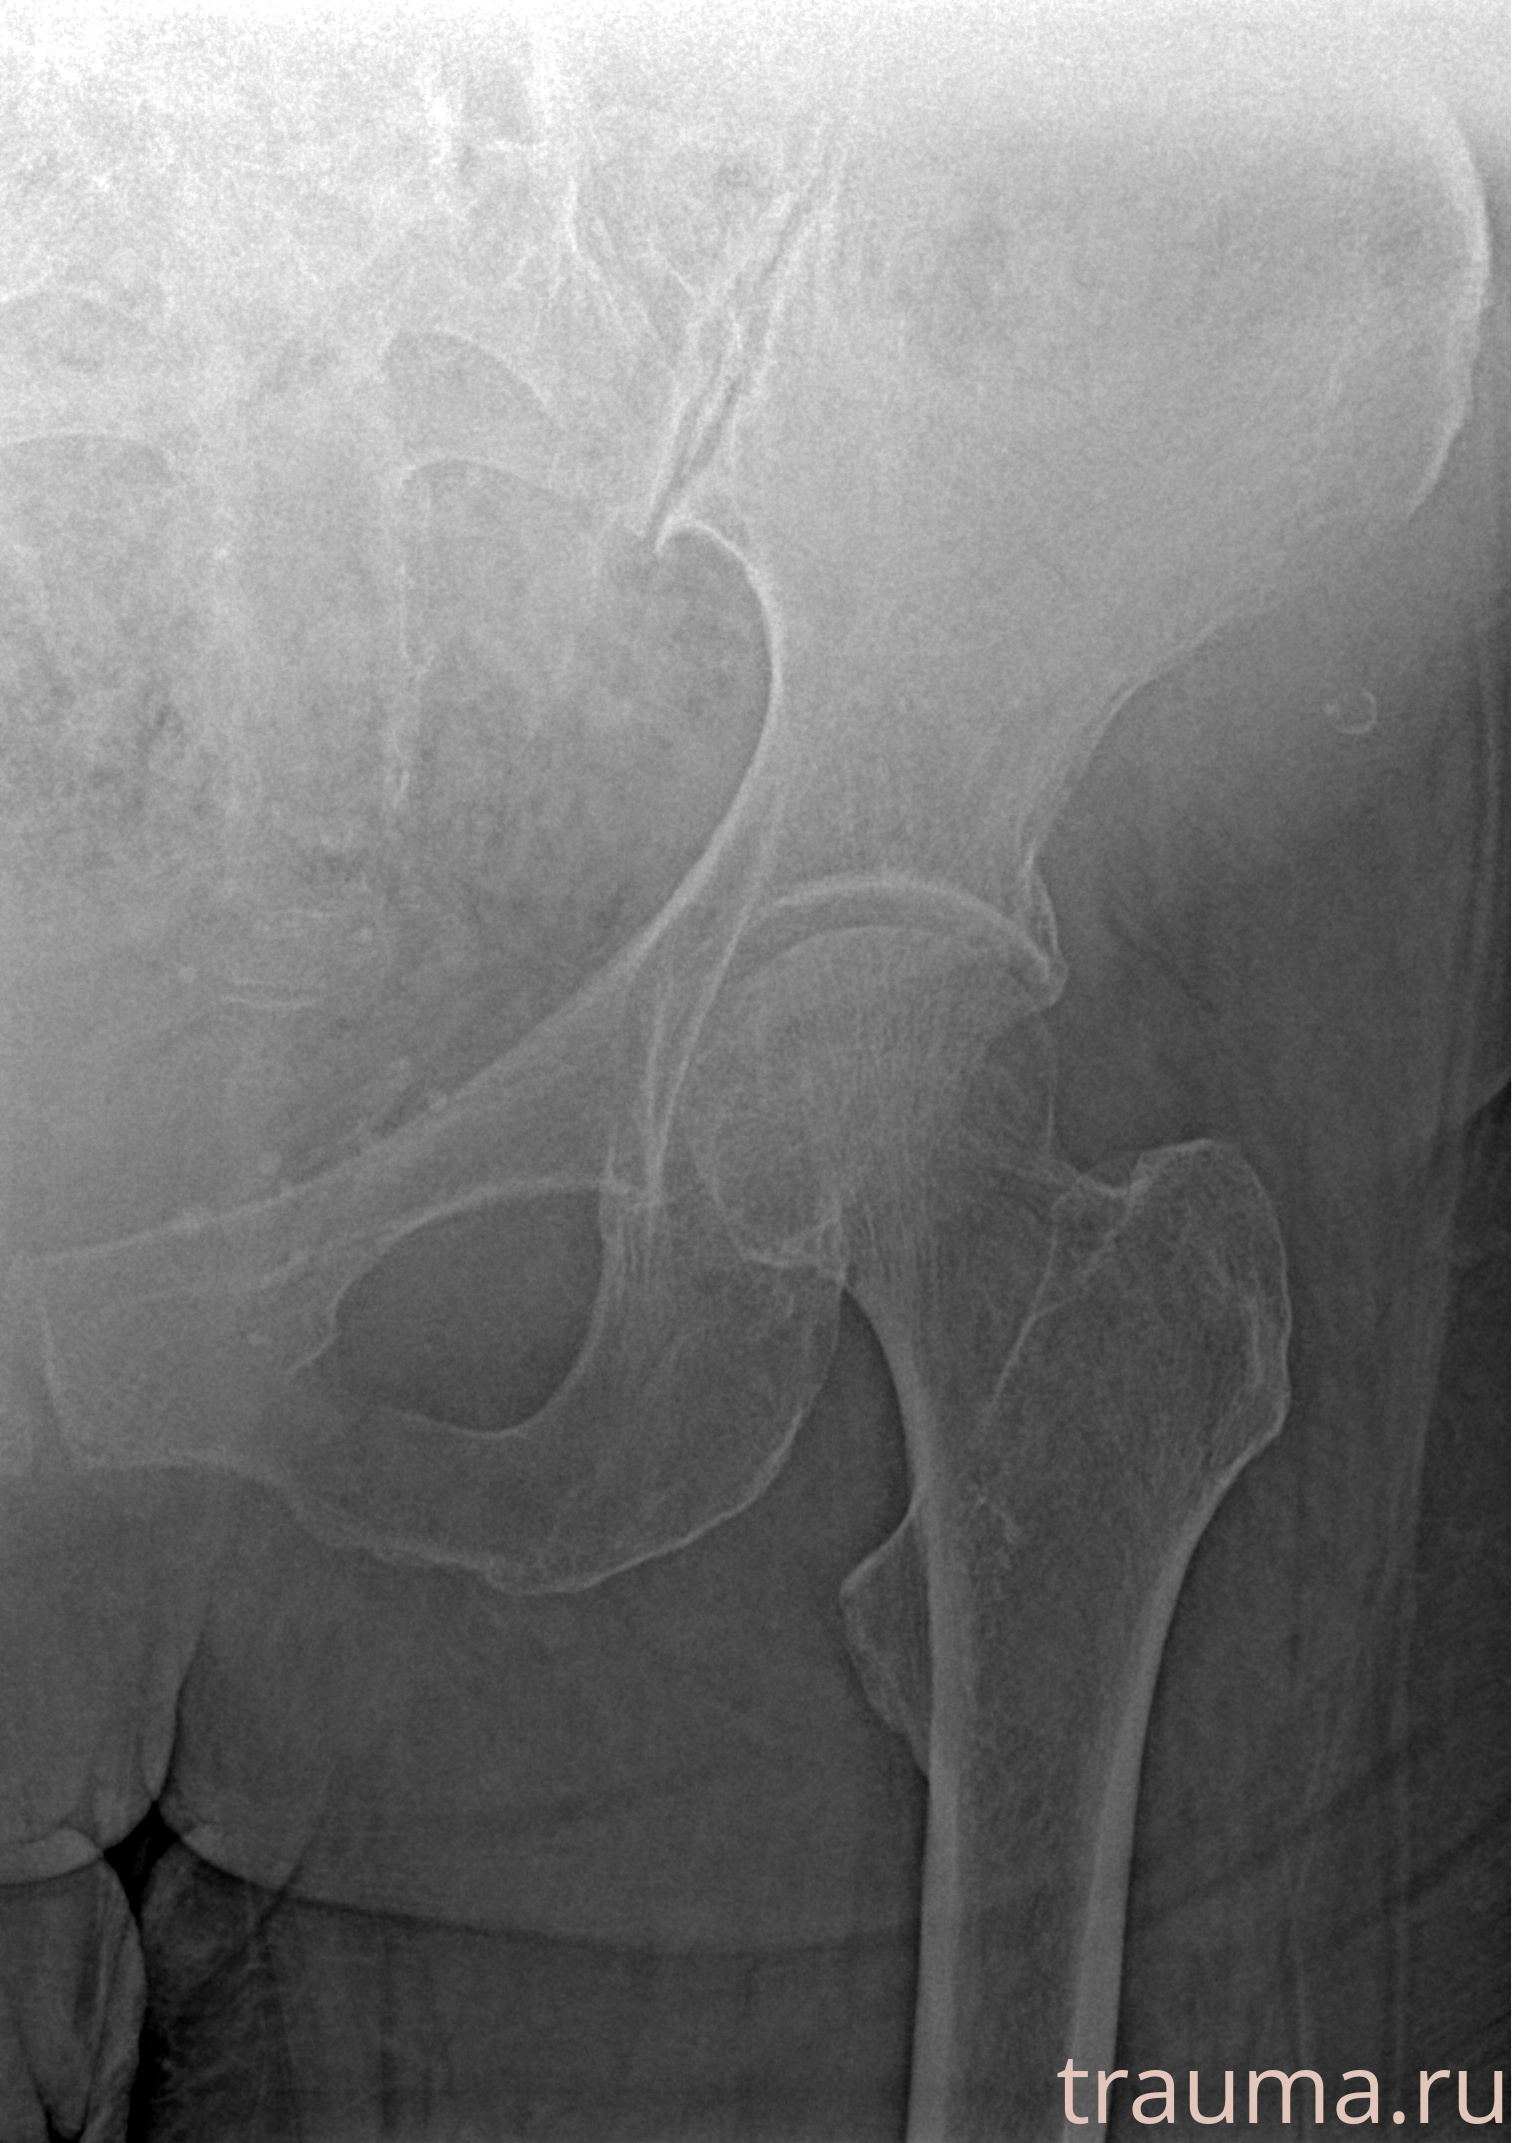

Первая помощь при переломе шейки бедра

Рентгенограммы

Рентген на дому: по вашему адресу приезжает врач-рентгенолог, травматолог-ортопед с мобильным рентгеновским аппаратом, проводит диагностику травмы или заболевания, делает необходимые рентгенограммы, дает рекомендации по дальнейшему лечению. Получить качественные снимки в домашних условиях возможно благодаря уникальной методике, разработанной МосРентген Центром для института  Склифосовского

при переломе шейки бедра и пневмонии от компании МосРентген Центр - партнера Института имени Склифосовского